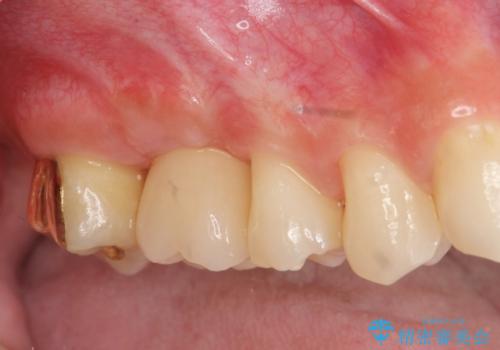

[歯周病治療] 歯周補綴 インプラント補綴

![[歯周病治療] 歯周補綴 インプラント補綴の症例 治療後](https://seimitsushinbi.jp/wp/wp-content/uploads/2020/03/93a1bf8bd8e0f11621dbb40f6f1d795c-500x350.jpg?v=1585494318)